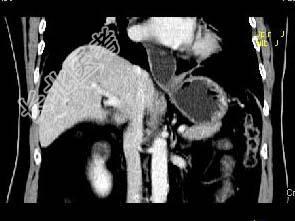

- 单项选择题根据所提供的图像,最可能的诊断是 ( )

A、肝血管瘤

B、局灶性结节增生

C、肝硬化再生结节

D、肝癌

E、肝转移癌